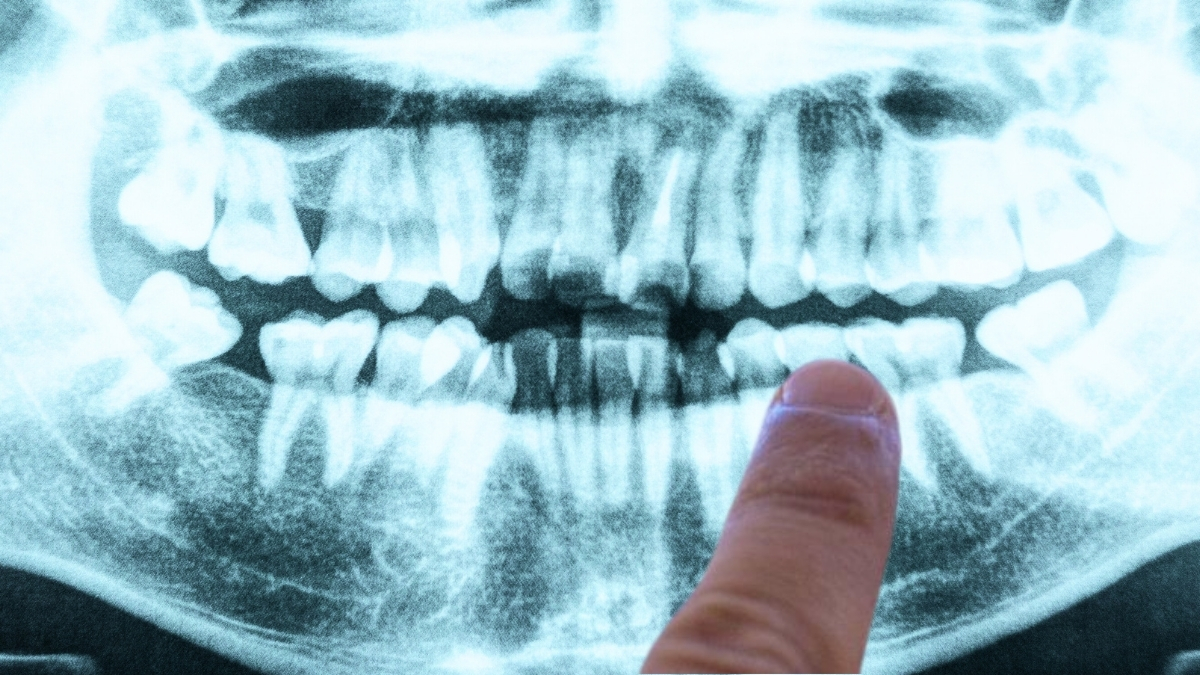

One such study, published in 2019, suggested what could be one of the most definitive leads yet for a bacterial culprit behind Alzheimer’s, and it comes from a somewhat unexpected quarter: gum disease.

In a paper led by senior author Jan Potempa, a microbiologist from the University of Louisville, researchers reported the discovery of Porphyromonas gingivalis – the pathogen behind chronic periodontitis (aka gum disease) – in the brains of deceased Alzheimer’s patients.

In separate experiments with mice, oral infection with the pathogen led to brain colonization by the bacteria, together with increased production of amyloid beta (Aβ), the sticky proteins commonly associated with Alzheimer’s.

In addition, the team identified toxic enzymes called gingipains secreted by the bacteria in the brains of Alzheimer’s patients, which correlated with two separate markers of the disease: the tau protein, and a protein tag called ubiquitin.

But even more compellingly, the team identified these toxic gingipains in the brains of deceased people who were never diagnosed with Alzheimer’s.

That’s important, because while P. gingivalis and the disease have been linked before, it’s never been known – to put it simply – whether gum disease causes Alzheimer’s, or whether dementia leads to poor oral care.

The fact that low levels of gingipains were evident even in people who were never diagnosed with Alzheimer’s could be a smoking gun – suggesting they might have developed the condition if they had lived longer.

“Our identification of gingipain antigens in the brains of individuals with AD and also with AD pathology but no diagnosis of dementia argues that brain infection with P. gingivalis is not a result of poor dental care following the onset of dementia or a consequence of late-stage disease,” the authors explained in their paper.

“But it is an early event that can explain the pathology found in middle-aged individuals before cognitive decline.”